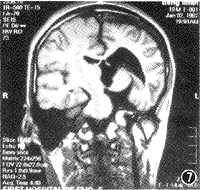

图7 MRI冠状面示左大脑脚萎缩,左侧脑室扩大

图8 MRI横断面示,左诊叶缺如,枕大池与第三脑室相通

图9 MRI示左大脑后动脉分支减少